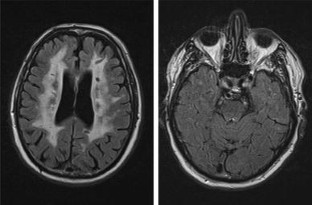

Fig. 1